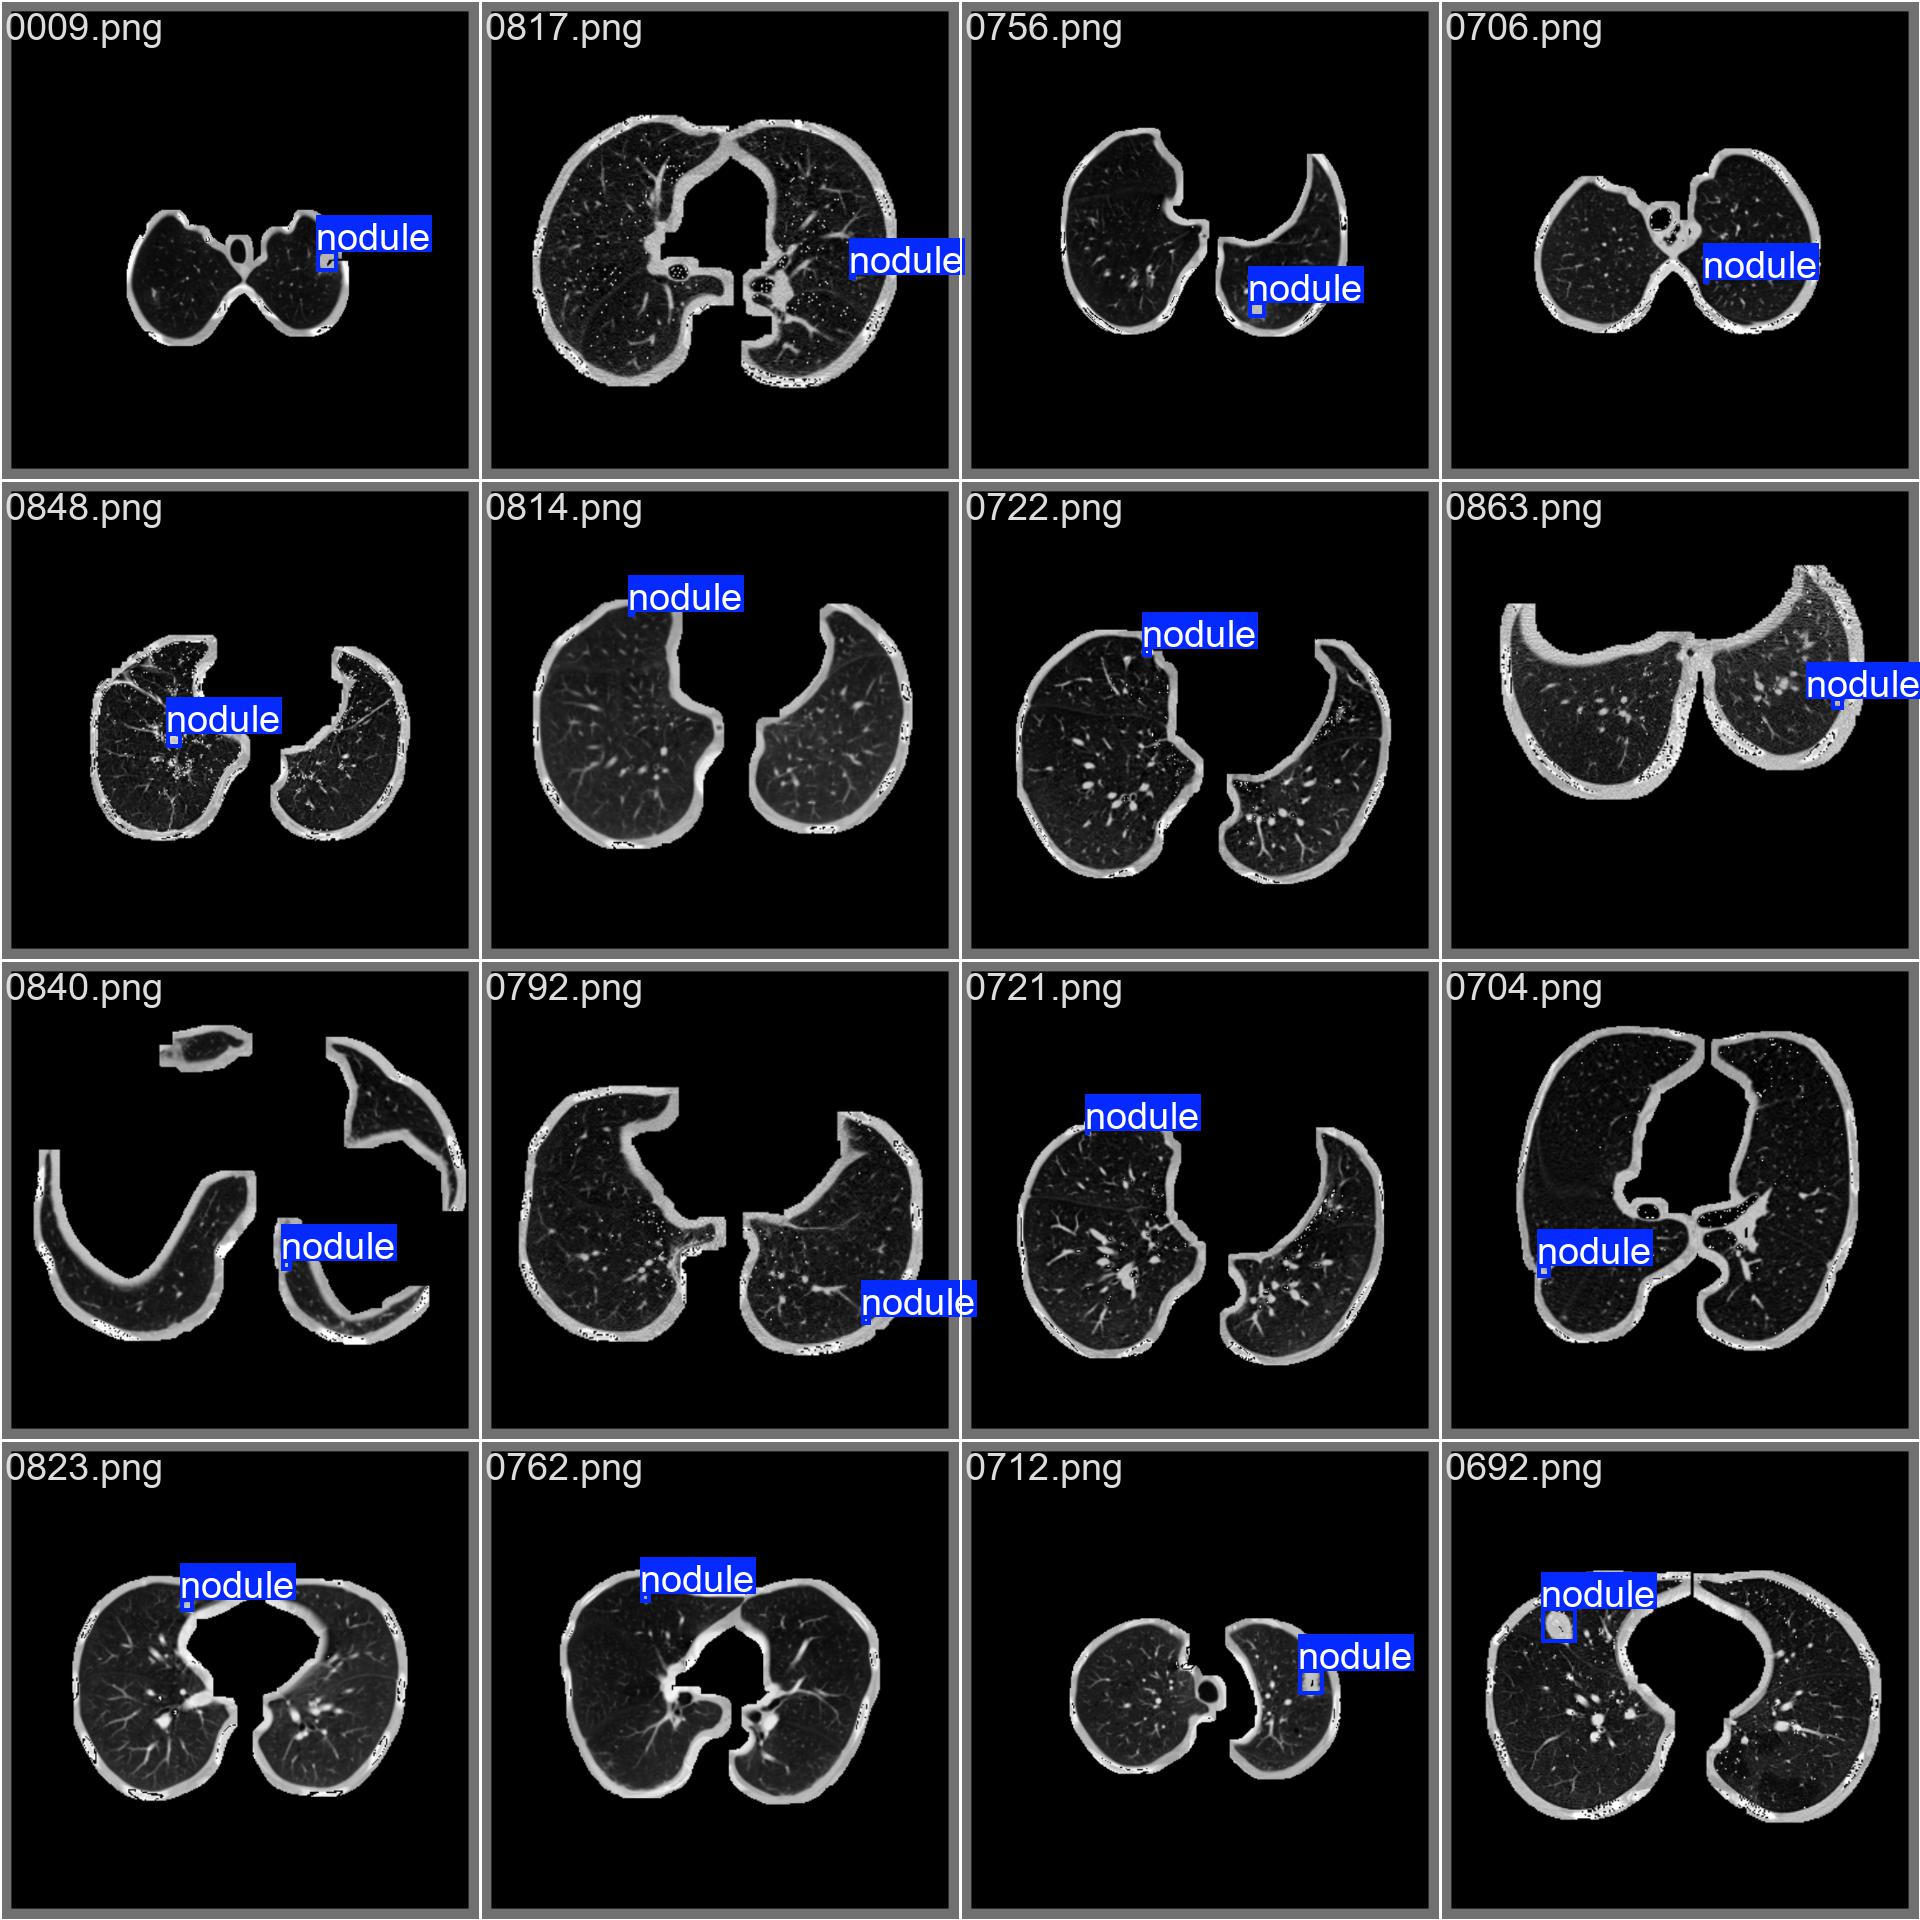

下面是数据集的部分示例。

当iou阈值为0.5的时候,模型在测试集上的map可以达到68.1%。下面是一个预测图像,可以看出,我们的模型可以有效的预测出这些尺度比较小的交通目标。